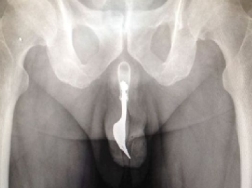

Stando al pezzo sull'"International Journal of Surgery", intitolato "Un corpo estraneo insolito nell'uretra", l'uomo aveva introdotto la forchetta di 10 centimetri, in metallo, dodici ore prima, ma non era stato più in grado di rimuoverla.

I medici, affrontando per la prima volta un caso del genere, "hanno valutato le varie operazioni possibili" e alla fine hanno estratto l'oggetto usando un forcipe e del lubrificante, con il paziente sotto anestesia totale.